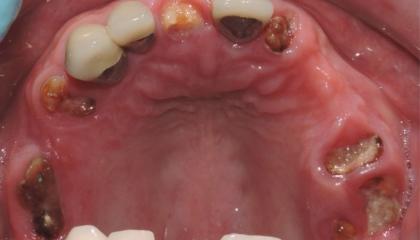

Before